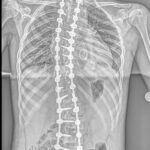

Lise öğrencisi Eren Sayın’ın, 4 yaşında kalp yetmezliği olduğu ortaya çıktı ve kalbindeki delik nedeniyle ilk ameliyatını oldu. 4 yaşında bu yana ilaç kullanan Eren, 1 yıl önce bu kez mitral kapak değişimi operasyonu geçirdi. Kalp rahatsızlığı ile birlikte skolyozu da bulunan Eren, ağrıları artından Ankara Etlik Şehir Hastanesi’ne başvurdu. Eren’in sırt bölgesinde 90, bel bölgesinde 70 dereceye ulaşan eğrilik tespit edildi. Eren, kalp kapağı ameliyatı nedeniyle kullandığı kan sulandırıcı ilaçlar kesilmeden biri 8 saat, diğeri 6 saat olmak üzere 2 seanslık riskli operasyonla skolyozdan kurtuldu. Eren, yüksek miktarda kan kaybı yaşamasına rağmen başarılı geçen operasyonun ardından sağlığına kavuştu.

Ameliyatı gerçekleştiren Etlik Şehir Hastanesi Ortopedi ve Travmatoloji Uzmanı Doç. Dr. Vedat Biçici, Eren’in kalp rahatsızlığı nedeniyle skolyozunun son dönemde hızlı ilerlediğinin tespit edildiğini söyleyerek, “Kalpteki problemlerinden dolayı riskli bir hastaydı. İlk ameliyatında ciddi kanaması olmasından dolayı ilk ameliyatını birinci seans olarak tamamlayamadan bitirmek zorunda kaldık. İmplantlarını yerleştirip, ameliyatı sonlandırdık. Genel durumu toparladıktan sonra birkaç hafta geçip, değerleri de normal değerlere geldikten sonra ikinci seans olarak tekrar ameliyata aldık. İkinci seansta omurgadaki düzeltme işlemlerini tamamlayıp operasyonumuzu bitirdik” diye konuştu.

Doç. Dr. Biçici, skolyoz cerrahisinin diğer cerrahilere göre daha riskli, daha zor olduğunu söyleyerek, “Çünkü omuriliğe çok yakın çalışmanız gerekiyor ve yerleştirdiğiniz implantlar yüzünden bazen milimetre düzeyinde yakın çalışıyorsunuz. Omurgayı düzeltirken omuriliğe hasar verme ya da omuriliğe bir problem oluşma ihtimali yüksek. Ondan dolayı riskli bir ameliyattır. Zaten cerrahi süresi uzun ve geniş bir alanda ameliyat yaptığınızdan dolayı bunlar hep riski artıran şeylerdir. Eren ayrıca kan sulandırıcı ilaç alıyor. Bunlar kesilemediğinden bu ilaçların etkisi altında ameliyata almak zorunda kaldık. Normalde bu ilaçlar ameliyat öncesinde kesilir, kanama riski azaltılır. Ama Eren’de bunu yapamadık. Bu da Eren’in ilk ameliyatta kan kaybını artırdı. İlk ameliyatta ciddi kan kaybı yaşadık, operasyonu yarıda bırakmak zorunda kaldık. Kan tablosu normal değerlere geldikten sonra ikinci seans ameliyata aldık. Onun için daha güvenli olacak şekilde iki aşamada ameliyatını tamamladık. Şu an durumu iyi. Fizik tedaviye başlayacak ve kademeli olarak normal hayatına dönecek” dedi.